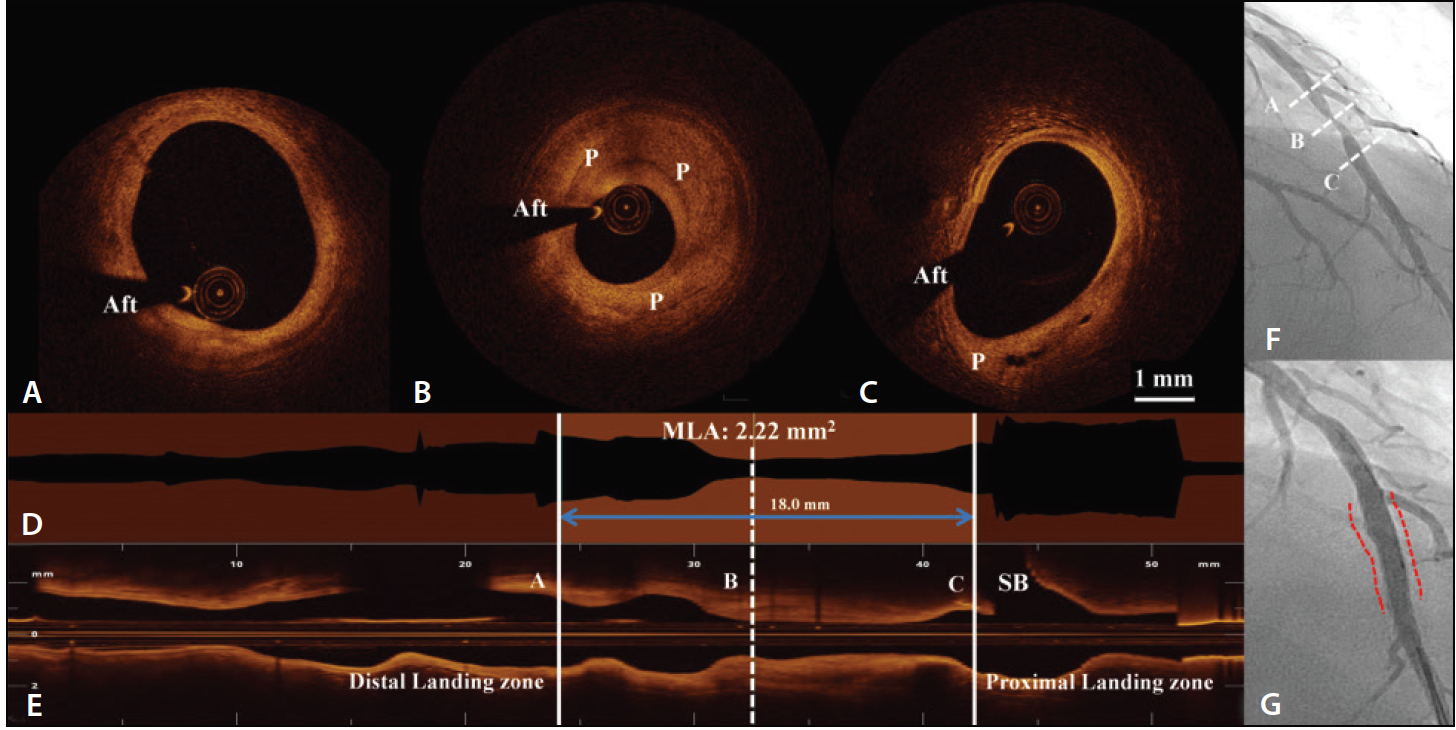

Figure 2. “Virtual PCI” planning. OCT images of the left anterior descending artery before scaffold implantation showing the distal landing zone (A), minimal lumen area (B), and proximal landing zone (C). OCT can assess lumen dimensions accurately, assess underlying plaque composition, and shows the location of the minimal lumen area in relation to the treated vessel on the lumen profile (D). In this way, OCT can guide scaffold implantation strategy by assessing the scaffold length (18 mm, in this example) required for optimal lesion coverage and avoiding SB ostia. The SB is seen on the longitudinal profile (E). The LAD is shown before (F) and after (G) implantation of a 3- X 18-mm Absorb BVS (dashed line). Aft, guidewire artifact.

There are also advantages to using OCT in the deployment of BRSs. OCT was one of the most useful techniques for the early evaluation of the Absorb BVS and its resorption process. New OCT probes are low-profile (2.6–2.7 F), flexible, coated with a hydrophilic layer, and the acquisition speed is at least 10 times higher when compared to IVUS. OCT catheters have a low delivery profile and can pass almost every lesion with few anatomical or patient exclusion criteria. The OCT imaging procedure is safe30 and fast, providing all necessary information in just seconds (Figure 2).31 The latest European Society of Cardiology guidelines on myocardial revascularization has already recommended OCT as a tool in selected patients to optimize stent implantation (level of evidence class II B, level C).29